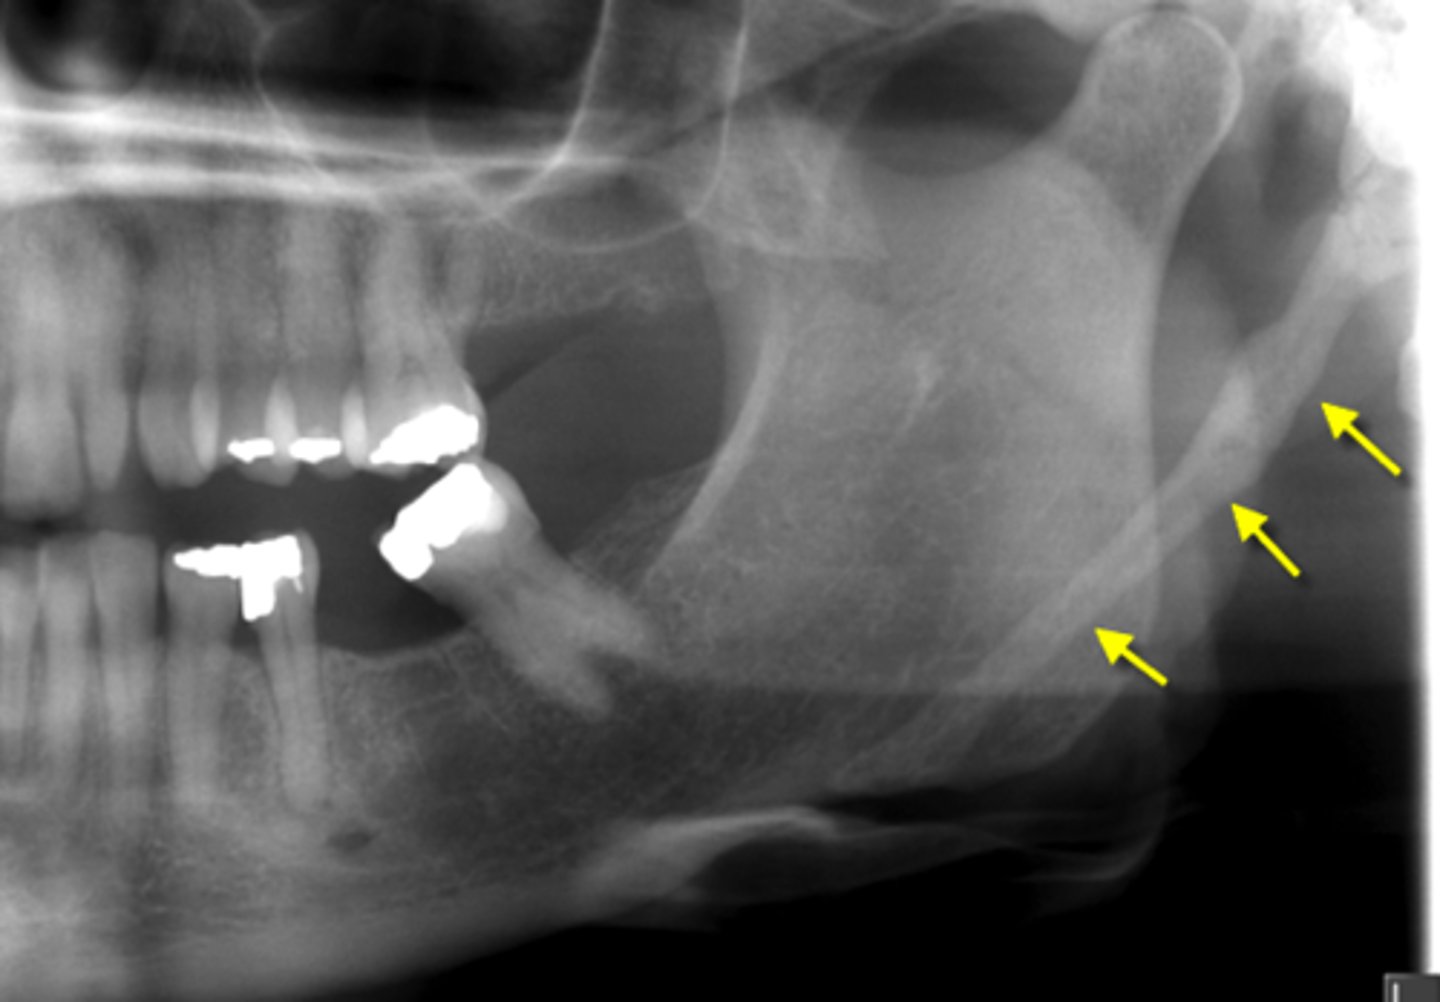

What is proliferative periostitis also known as?

Garre's Osteomyelitis

What is a characteristic appearance of Garre's Osteomyelitis?

Onion skin

Who is more affected by Garre's Osteomyelitis?

Females, younger